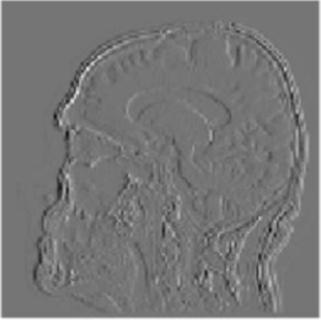

Gray matter atrophy has been found to be responsible for MCI and AD progression (Apostolova et al., 2007). Pre-processing also standardizes the images. (Friston et al., 1994). Thus, pre-processing via segmentation and smoothing to capture just the gray matter of the MRI scans is necessary. The MRI scans were segmented using the Computational Anatomy Toolbox 12 (CAT 12) (Rajapakse et al., 1997) toolbox of MATLAB. These programs segmented the MRI images into grey matter, white matter, and cerebrospinal fluid. Figure 2 shows an unmodified MRI and a segmented MRI, which demonstrates the differences between them. After segmentation, the grey matter from each MRI scan was smoothed using the Statistical Parametric Mapping 12 (SPM12) (Friston et al, 1994) toolbox of MATLAB. These smoothed grey matter images were then sent for feature extraction.

To display how the DWT performs on an MRI scan, the 2-D DWT performed on a 2-D slice of a 3-D MRI scan. Four subbands were generated by a low-pass or high-pass filter being performed on each of the two dimensions in 2-D image. Each subband is represented as a two-letter key, representing what subbands are in which dimension. An “a” represents an approximation subband produced by a low-pass filter and a “d” represents a detail subband produced by a high-pass filter. Figure 2 shows the four resulting subbands after this procedure.

Figure 2. The visualization of the 2-D DWT performed on a model slice with all four subband patterns: 2A: Approximation subbands in both dimensions (aa); 2B: approximation subbands in the horizontal dimension and detail subbands in the vertical dimension (ad); 2C: Detail subbands in the horizontal direction and approximation coefficients in the vertical direction (da); 2D: Detail subbands in both dimensions (dd).